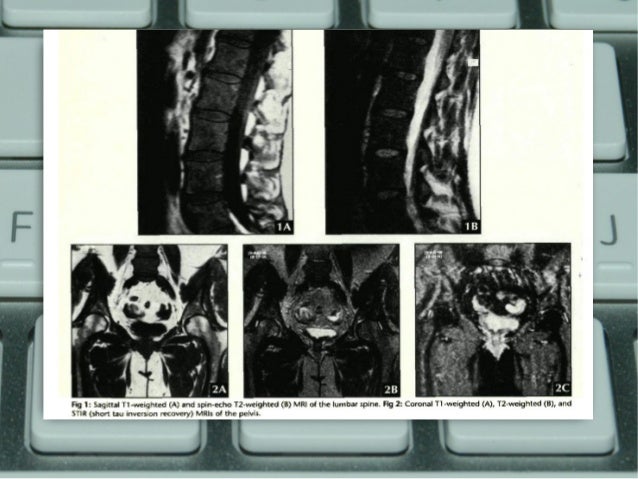

Mri case study presentation image This image shows mri case study presentation.

You can use this template to teach the employees about the company values. His mri showed a large heterogeneously enhancing tumor in the corpus callosum with severe mass effect. P previous exams -mri 2017 -transthoracic echocardiogram2011 patient prep b s k picture courtesy of c e e exam . Mri case study #2 mri lead handling and patient management dr. There are many templates to describe the case study of your project and your client.